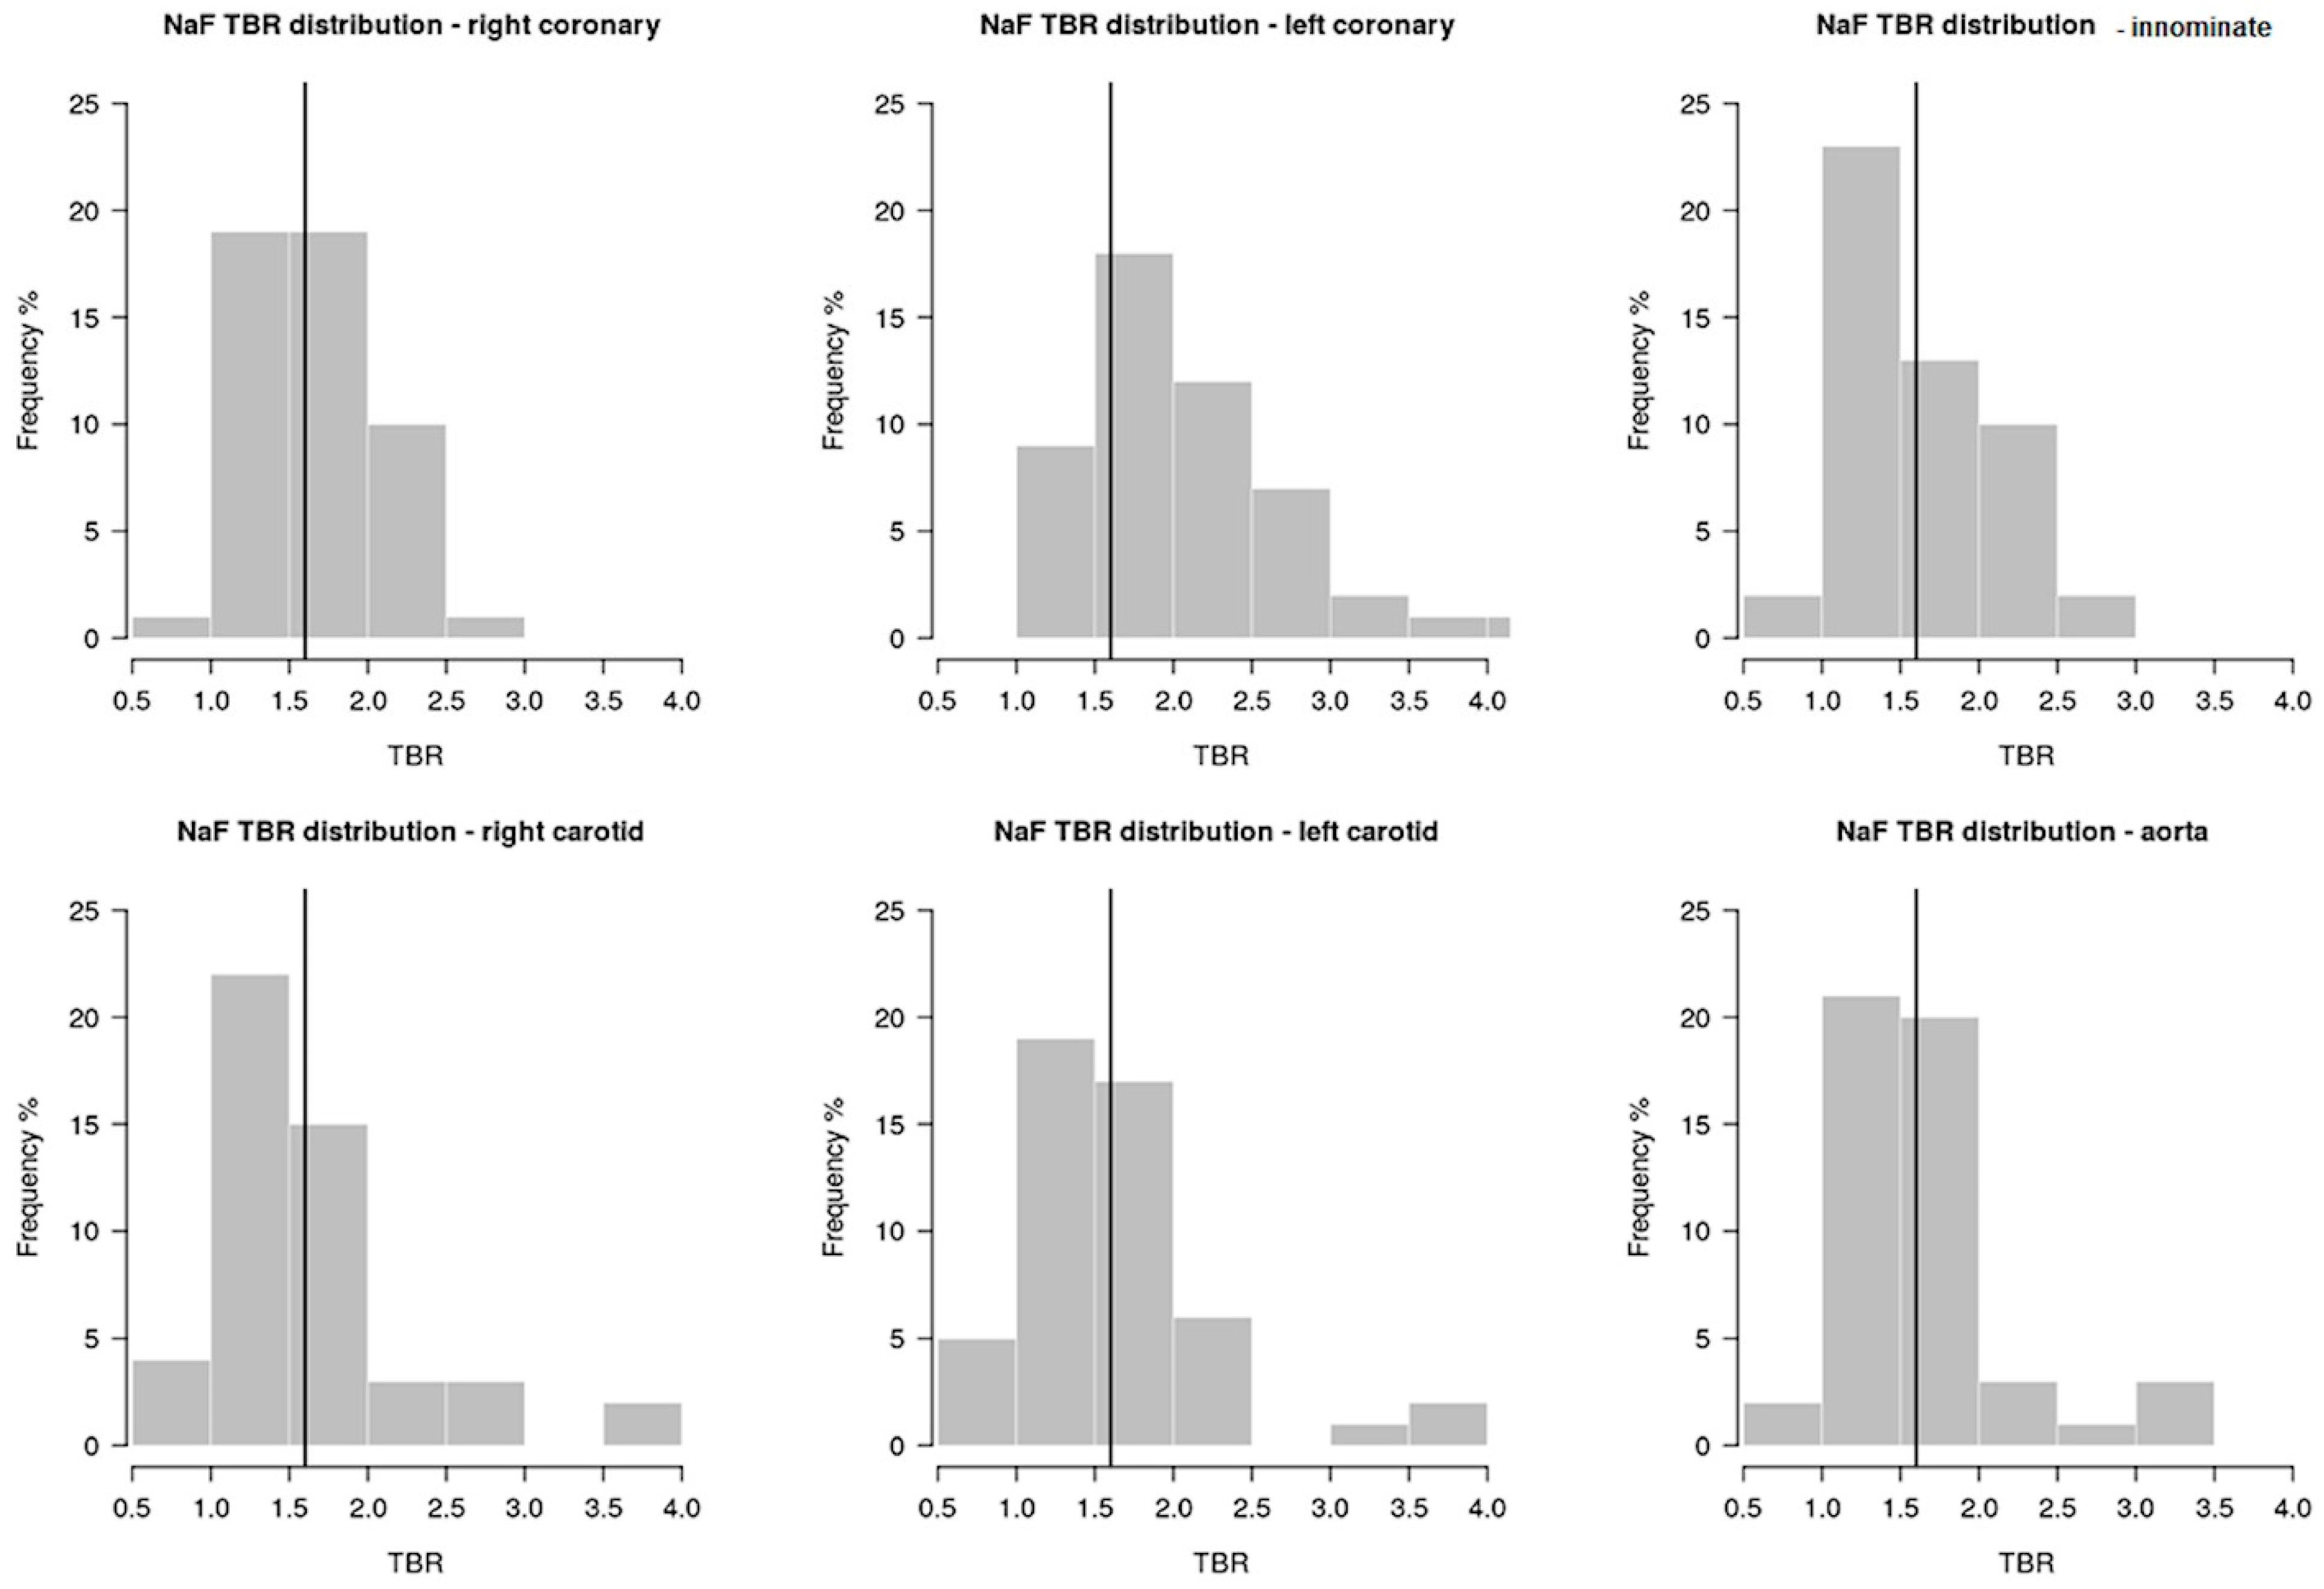

2. Results

4.3.2. Positron Emission Tomography with 18F-Sodium-Fluoride

4.3.3. Image Analysis